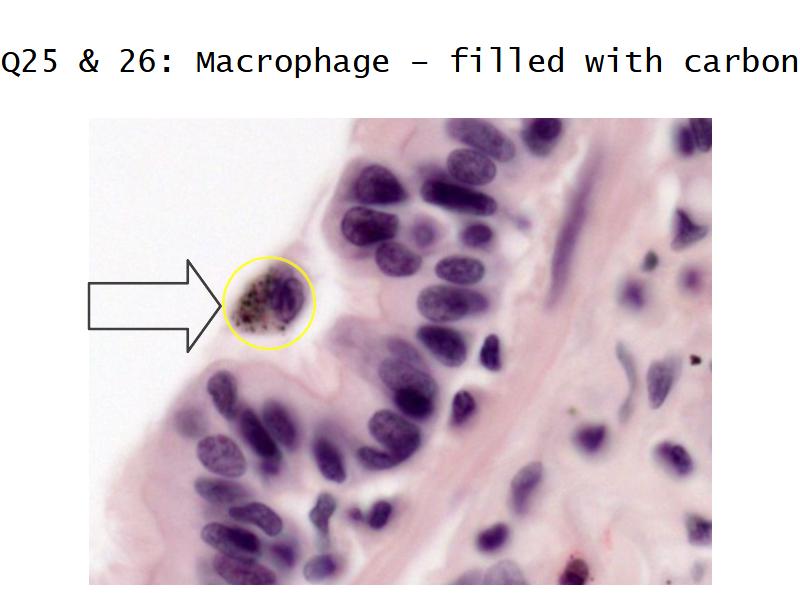

Slides: Respiratory System

- Slide 71: Nostril

- Slide 72 & 74: Lung

- Slide 73: Trachea

- Slide 108: Olfactory epithelium

- Slide 111: Epiglottis

Respiratory epithelium

- Pseudostratified

- Ciliated

- Columnar

- Epithelium with

- 4 Cells

- Ciliated columnar cells

- Non-ciliated columnar cells

- Goblet cells

- Basal cells